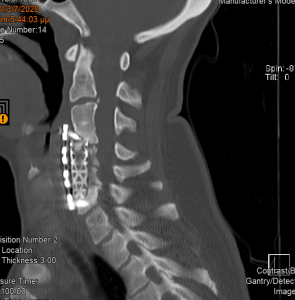

Ο απεικονιστικός έλεγχος με μαγνητική και αξονική τομογραφία της σπονδυλικής στήλης ανέδειξε εικόνα σωματεκτομής Α5, Α6 και μερικώς και Α7. Υπήρχε χαλάρωση των βιδών που καθήλωναν την πλάκα. Συνολικά εικόνα ψευδάρθρωσης και πίεσης επί του νωτιαίου μυελού και των αυχενικών ριζών (κυρίως Α7 δεξιά)

Διενεργήθηκε αρχικά οπίσθια σπονδυλοδεσία με διαυχενικές βίδες Α4, βίδες στα πλάγια ογκώματα Α5 και διαυχενικές βίδες Α7 και Θ1 ενώ έγινε και τρηματεκτομή Α6/7 δεξιά.

Στη συνέχεια, αφαίρεση της πρόσθιας πλάκας, ολοκλήρωση της σωματεκτομής Α5 & Α6, απελευθέρωση του νωτιαίου μυελου, πρόσθια δισκεκτομή Α7/Θ1 και τοποθέτηση πρόσθιας πλάκας Α4-Θ1.

Αρχικά έγινε οπίσθια σπονδυλοδεσία προκειμένω να στηριχθεί ο αυχένας της ασθενούς και να μειωθούν τα άλγη τα οποία οφείλονταν στην “αστάθεια” της αυχενικής μοίρας. Παράλληλα, διενεργήσαμε και οπίσθια τρηματεκτομή ώστε να εξασφαλίσουμε την απελευθέρωση της δεξιάς Α7 ρίζας, η οποία δημιουργούσε πόνο στην ασθενή. Όπως φαίνεται στη μετεγχειρητική αξονική τομογραφία, οι βίδες στους αυχένες του Α4 σπονδύλου τοποθετήθηκαν με ακρίβεια χιλιοστού. Σ’ αυτό, σημαντική ήταν η βοήθεια του διεγχειρητικού νευροπλοηγού σπονδυλικής στήλης με το πιο σύγχρονο σύστημα απεικόνισης (Ο-arm II)